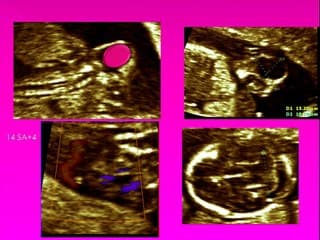

L'auteur rappelle l'aspect normal de la coupe de 3 vaisseaux: de droite à gauche et d'arrière en avant: la VCS, la crosse du canal artériel (CA) et la crosse de l'aorte horizontale. Avec un gradient de taille et un flux Doppler antérograde dans les deux crosses.Ainsi que l'aspect normal de la coupe 4 cavités et des voies d'éjection droite et gauche.- La découverte d'une artère pulmonaire plus petite que l'aorte associée à un flux rétrograde dans l'AP, un VD hypertrophié, une fuite -tricuspide, un anneau tricuspide large, ainsi que des fistules coronaires en Doppler couleur dans le VD fait porter le diagnostic d'APSI ou (atrésie pulmonaire à septum intact) ou de sténose pulmonaire à SI. Le pronostic est basé sur le Z Score de la taille de l'anneau tricuspide.- Autre diagnostic devant une artère pulmonaire plus petite que l'aorte avec un axe du coeur inhabituel dans le thorax, une CIV avec aorte à cheval, un septum conal basculé sous l'AP, fait évoquer une pathologie conotroncale de type Tétralogie de Fallot. Le pronostic dépendra de la taille des artères pulmonaires._ Enfin une petite AP peut être associée à une anomalie de développement de tous les étages du coeur avec une TGV, ou un ventricule unique sous 2 valves auriculo-ventriculaires bien équilibrées. Cardiopathie qui sera incurable.